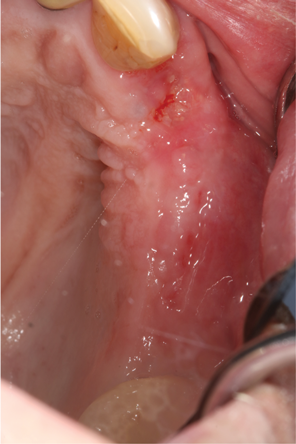

Fig 16. In a separate case, prepared L-PRF for use as a biologic bandage at palatal donor site after FGG harvest is shown (Fig 15); intraoperative photograph (Fig 16) shows L-PRF membrane sutured at palatal wound site after FGG harvest for postoperative pain control.

Figure 16

Another clinical scenario in which the use of PCs may be beneficial during soft-tissue grafting procedures is the use of PRF as a biologic bandage at palatal donor sites where CTG or free gingival graft (FGG) harvest has occurred. PRF application to a palatal donor site (Figure 15 and Figure 16) resulted in faster healing and nearly complete wound epithelialization 1-week postoperatively with minimal clinical inflammation compared to incomplete wound closure 2 weeks postoperatively where PRF was not used.42